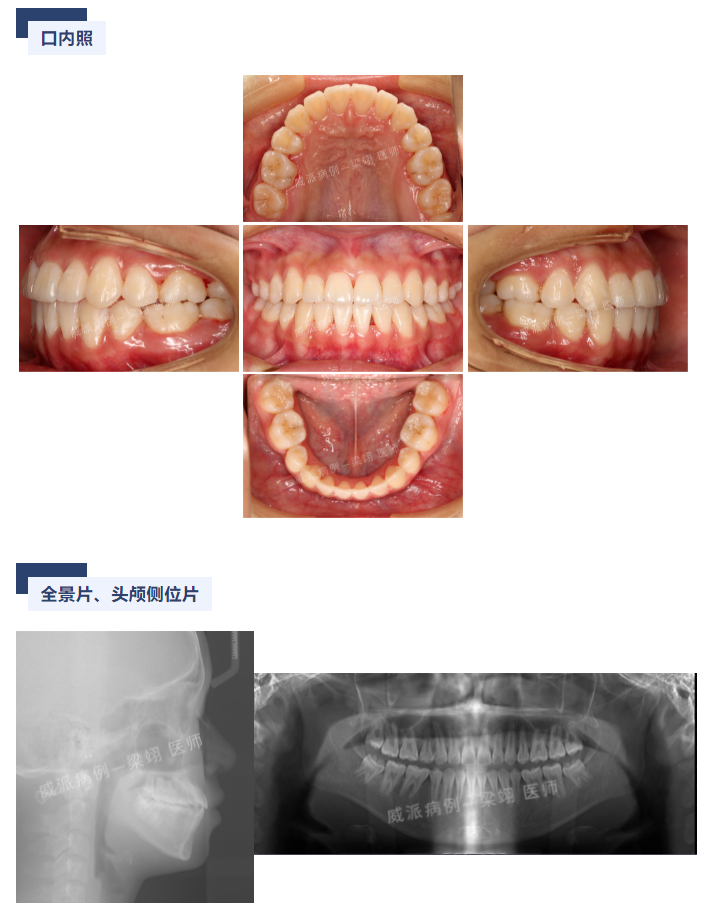

威派病例分享丨一例 III 类治疗:拔牙横向调整病例 (梁翊)